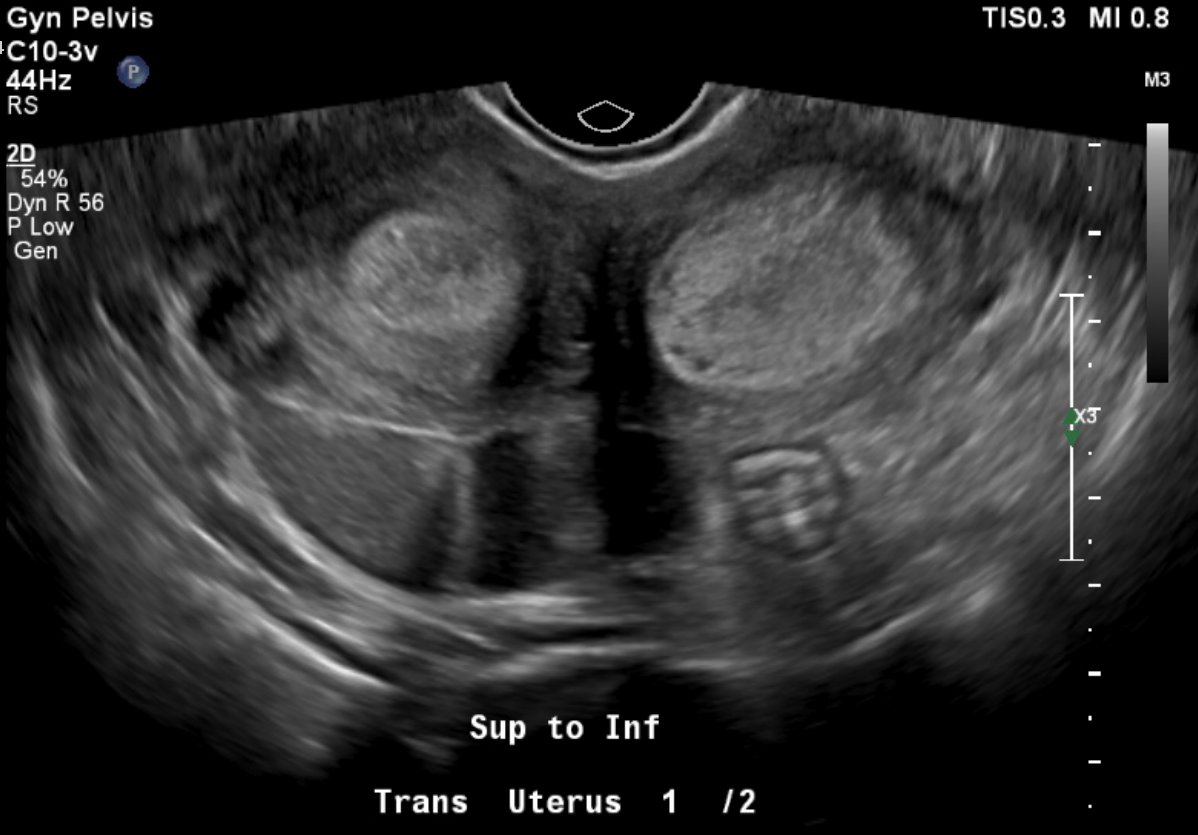

Does this patient have a normally developing pregnancy by ultrasound?

Answer:

No, the snowstorm appearance in both uterine cavities is not consistent with her quantitative hcg; there is also no evidence of a gestational sac or normal intrauterine pregnancy.

Further pathology of this patient’s uterine contents revealed immature chorionic villi in the left uterine horn with endometrial tissue in the right uterine horn. The report also specified that a very early complete hydatidiform mole and invasive mole must be ruled out, therefore lacking a definitive diagnosis. Clinically, the presentation was consistent with a molar pregnancy.

This patient had two uncommon pathologies: presumed gestational trophoblastic disease and uterine didelphys. Gestational trophoblastic disease encompasses a spectrum of premalignant to malignant gestational tissue. Rates are difficult to obtain, as there seems to be wide temporal variation, but estimates for hydatidiform mole in particular are estimated to be between 0.57 and 2 per 1000 pregnancies. Ultrasound and laboratory findings such as quantitative beta HCG are mainstays of early identification and treatment. Ultrasound is not very sensitive as a diagnostic modality, but it does have high positive predictive value.1 In this patient, the mismatch in quantitative beta HCG value, last menstrual period date, ultrasound findings, as well as the patient’s postpartum period combined with depo-provera birth control led our team to be exceedingly concerned for gestational trophoblastic disease (GTD). Unchecked, GTD can lead to increased uterine size and bleeding, to endocrine abnormalities, and even to invasive central nervous system lesions and death; however, with treatment and early diagnosis complete resolution nears 100% in women.2 It is important to remember to include a chest x-ray in your workup for screening in a patient with suspected gestational trophoblastic disease to determine staging and appropriate treatment. For example, if lung lesions are visible, the patient would require CT Chest/Abdomen/Pelvis and brain MRI to determine staging.3 If found to have metastatic disease, these patients likely need chemotherapy.4 This changes the level of subspecialty care the patient needs.